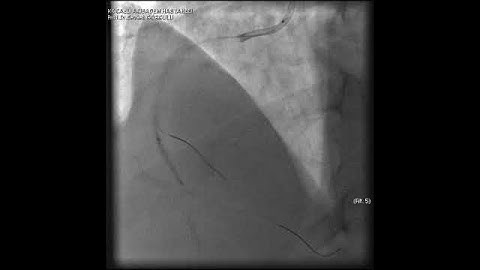

Complex PCI for RCA CTO with bifurcation at distal cap video 1